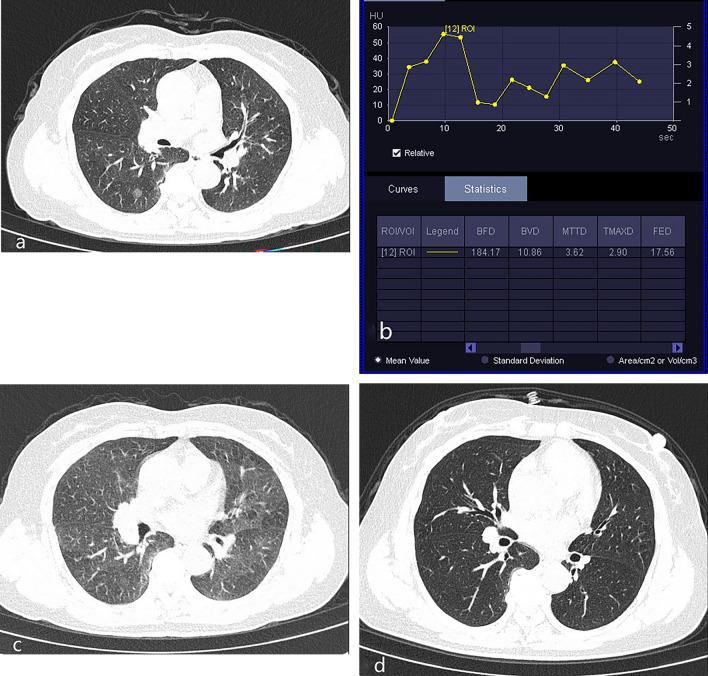

This study aimed to evaluate the value of low-dose dual-input computed tomography perfusion (CTP) imaging in the differential diagnosis of benign and malignant pulmonary ground-glass opacity nodules (GGO). A retrospective study was conducted in patients with GGO who underwent CTP in our hospital from January 2021 to October 2023. All nodules were confirmed via pathological analysis or disappeared during follow-up. Postprocessing analysis was conducted using the dual-input perfusion mode (pulmonary artery and bronchial artery) of the body perfusion software to measure the perfusion parameters of the pulmonary GGOs. A total of 101 patients with pulmonary GGOs were enrolled in this study, including 43 benign and 58 malignant nodules. The dose length product of the CTP (348 mGy.cm) was < 75% of the diagnostic reference level of the unenhanced chest CT (470 mGy.cm). The effective radiation dose was 4.872 mSV. The blood flow (BF), blood volume (BV), mean transit time (MTT), and flow extraction product (FEP) of malignant nodules were higher than those of the benign nodules (p < 0.05). The FEP had the highest accuracy for the diagnosis of malignant nodules (area under the curve [AUC] = 0.821, 95% confidence interval [CI]: 0.735-0.908) followed by BV (AUV = 0.713, 95% CI 0.608-0.819), BF (AUC = 0.688, 95% CI 0.587-0.797), and MTT (AUC = 0.616, 95% CI 0.506-0.726). When the FEP was ≥ 19.12 mL/100 mL/min, the sensitivity was 91.5% and the specificity was 62.8%. To distinguish between benign nodules and malignant nodules, the AUC of the combination of BV and FEP was 0.816 (95% CI 0.728-0.903), whereas the AUC of the combination of BF, BV, MTT, and FEP was 0.814 (95% CI 0.729-0.900). Low-dose dual-input perfusion CT was extremely effective in distinguishing between benign from malignant pulmonary GGOs, with FEP exhibiting the highest diagnostic capability.

本研究旨在评估低剂量双输入计算机断层灌注(CTP)成像在鉴别肺磨玻璃密度结节(GGO)良恶性中的价值。本回顾性研究纳入了 2021 年 1 月至 2023 年 10 月在我院行 CTP 的 GGO 患者。所有结节均经病理分析证实或随访中消失。采用体部灌注软件的双输入灌注模式(肺动脉和支气管动脉)对肺 GGO 的灌注参数进行后处理分析。本研究共纳入 101 例肺 GGO 患者,其中良性 43 例,恶性 58 例。CTP 的剂量长度乘积(348 mGy.cm)<未增强胸部 CT 诊断参考水平(470 mGy.cm)的 75%。有效辐射剂量为 4.872 mSV。恶性结节的血流量(BF)、血容量(BV)、平均通过时间(MTT)和血流提取产物(FEP)均高于良性结节(p<0.05)。FEP 对恶性结节的诊断具有最高的准确性(曲线下面积[AUC]为 0.821,95%置信区间[CI]:0.735-0.908),其次是 BV(AUC 为 0.713,95%CI 0.608-0.819)、BF(AUC 为 0.688,95%CI 0.587-0.797)和 MTT(AUC 为 0.616,95%CI 0.506-0.726)。当 FEP≥19.12 mL/100 mL/min 时,灵敏度为 91.5%,特异性为 62.8%。为鉴别良恶性结节,BV 和 FEP 联合的 AUC 为 0.816(95%CI 0.728-0.903),而 BF、BV、MTT 和 FEP 联合的 AUC 为 0.814(95%CI 0.729-0.900)。低剂量双输入灌注 CT 对鉴别肺 GGO 的良恶性非常有效,FEP 的诊断能力最高。